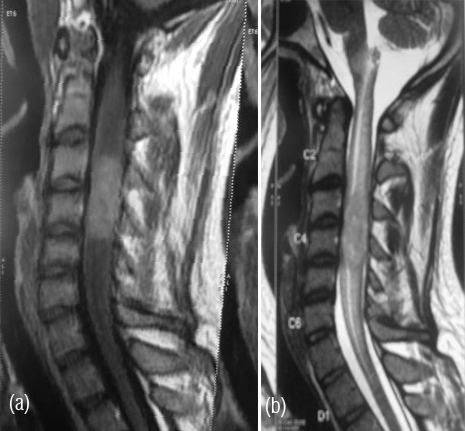

Post operatively, MRI brain and screening of entire spine was done which revealed residual lesion in suprasellar region and interpeduncular cistern. Another intramedullary lesion at C3-C4 level was detected causing focal cord expansion and displacement of cord anteriorly suggesting metastasis.

Figure 3a,b: MR spine – An elongated cylindroid space occupying lesion in cervical cord.

Metastatic work up also included chest radiograph, cerebrospinal fluid (CSF) cytology for malignant cells, radionuclide bone scan, bone marrow examination and ultrasound sonography (USG) abdomen, which did not reveal any other metastatic deposits outside the CNS.

Patient was treated with adjuvant radiation therapy to entire craniospinal axis + a focal boosts to residual suprasellar and spinal lesions followed by adjuvant chemotherapy and is disease free at 6 months follow-up.